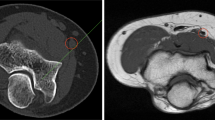

After measuring the distances, two additional parameters were defined using the distances measured above. The ratios of B to A (B/A) and D to C (D/C) indicate the relative position of the EP of the AIN in the entire forearm and the relative position of the AIN between the ulna and the radius, respectively. Figure 2 shows an example of the ultrasonographic images obtained from a participant’s forearm.

Ultrasonographic image of the distal volar forearm at the level of the entry point of the AIN into the PQ. AIA: anterior interosseous artery; AIN: anterior interosseous nerve; FCR: flexor carpi radialis; FDP: flexor digitorum profundus; FDS: flexor digitorum superficialis; FPL: flexor pollicis longus; PL: palmaris longus; PQ: pronator quadratus; R: radius; U: ulna.